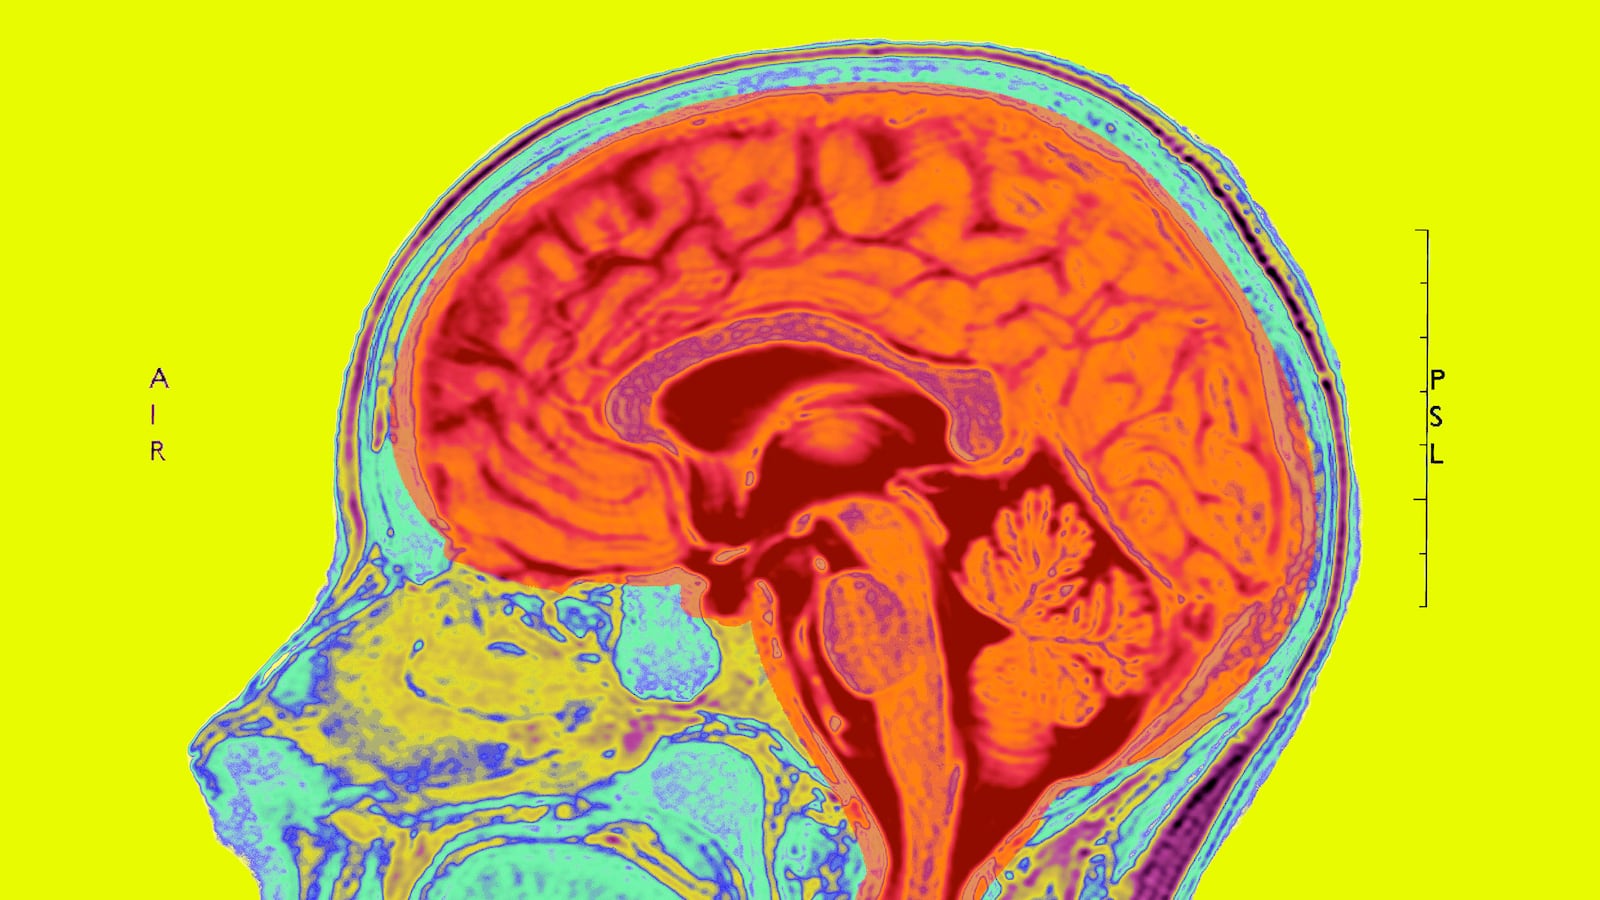

Like the cerebrum, the cerebellum has two hemispheres, separated by a structure called the vermis. Though it makes up only about 10 percent of the brain’s mass, 50 percent of the brain’s neurons are found there. Its main role is commonly thought to be coordinating our movements. When I’m doing a neurological exam on a patient, I’ll check for damage to the cerebellum by testing patients’ balance and their ability to perform rapid alternating motions.

However, according to Dr. Samuel Wang and his co-authors, the cerebellum may play a much larger role in shaping our brains’ functions beyond our motor abilities. In a detailed review of existing research, Dr. Wang, an associate professor of molecular biology and neuroscience at Princeton University, puts forth the theory that the cerebellum is responsible for helping developing minds process complex sensory information necessary to form normal social relationships. In cases where something goes awry in this process, other structures in the brain are affected, and ASDs may result.